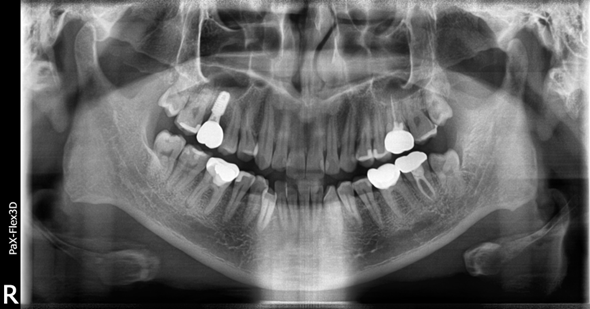

(전) 2022-05-10 (후) 2022-11-14

상악동거상술과 뼈이식, 임플란트 식립을 완료하고 3개월 후에 보철까지 올려 최종적으로 치료를 마쳤습니다.